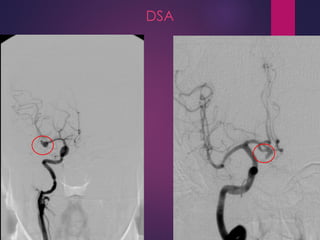

CEREBRAL ANGIOGRAPHY (DSA)

 Gold standard for evaluation of cerebral aneurysm (80-85%

sensitivity)

 Useful in cases of diagnostic uncertainty (after CT and LP)

 Can provide surgical information in the setting of SAH:

 Cerebrovascular anatomy

 Aneurysm location & source of bleeding

 Aneurysm size/shape/orientation of dome and neck

 Relation to the parent/perforating arteries

 Presence of multiple or mirror aneurysms

 If cerebral angiography findings are negative (10-20%) a

repeat test should be performed after 10-21 days

 May be useful to evaluate for possible cerebral vasospasm

DSA